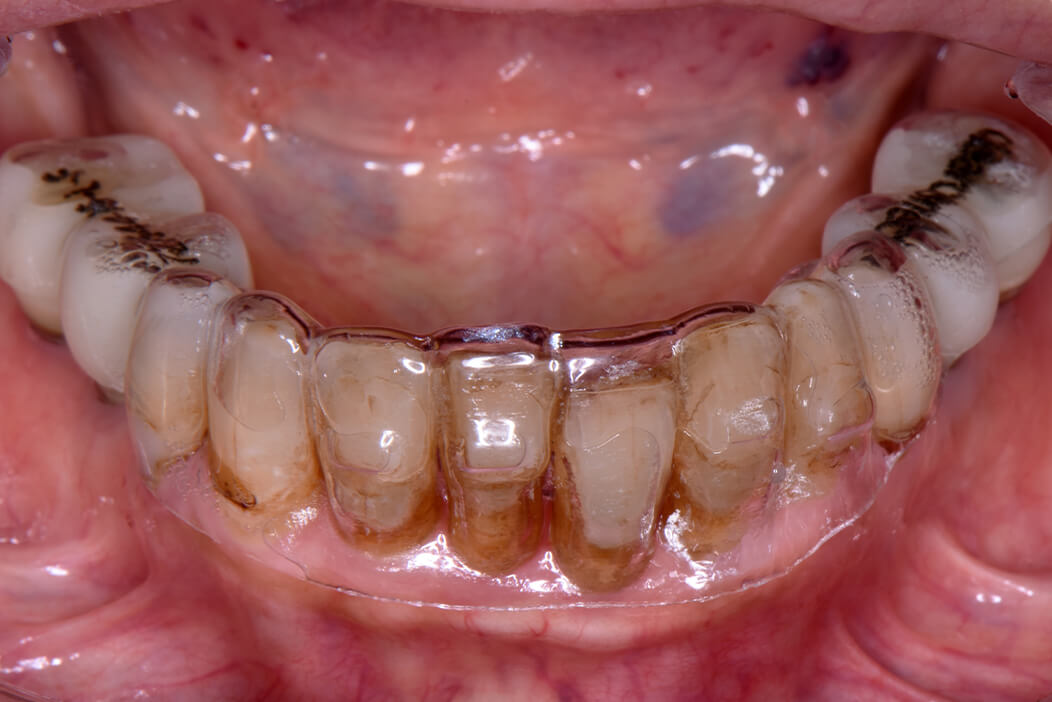

女性/70代

費用/2,277,000円

治療期間/4ヶ月

治療内容の詳細/

下顎を固定式の歯にしたいということでインプラント治療を希望。

術前のX線、CT撮影により下顎残存歯の保存が難しいため、抜歯して即時にインプラント治療を行い、同日に仮歯を入れて噛めるようにする即時荷重治療の治療計画を立てました。インプラント治療のシミュレーションを行い、保存不可能な歯牙を抜歯後、コンピューターガイデッドサージェリーを用いてストローマン社製BLXインプラントを適切な位置に4本埋入し、即日に仮歯を装着する即時荷重治療を行いました。約3ヶ月後口腔内スキャナーでデジタル印象を行い、スクリュー固定式のジルコニアセラミックブリッジを作成し装着しました。患者様は歯が無い時期がなく、食事等普段の生活に支障はなく過ごすことが出来ました。

患者様はインプラントのブリッジがよく噛めるので、上顎の入れ歯もインプラントにしたいということで現在治療中です。